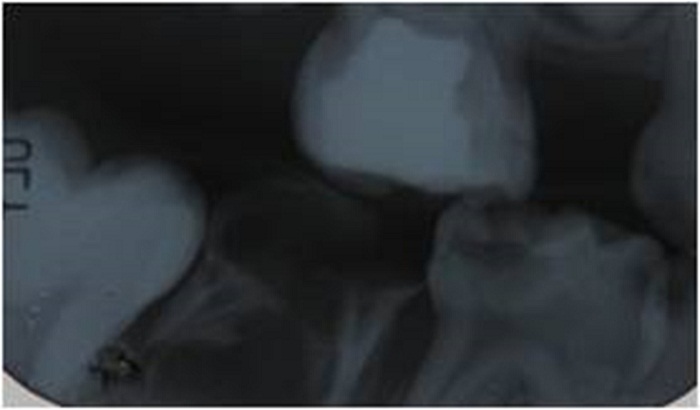

Durante la anamnesis, la madre refirió que el niño sufría desde los 2 años de edad de episodios repetitivos de broncoespasmo. Durante el examen de la cavidad oral, se observaron labios hipodróticos, mucosas humectadas, frenillos bien implantados, paladar normal, lengua saburral, piso de boca permeable y periodonto sano. El paciente presentaba caries en 11 dientes e higiene bucal deficiente. El estudio radiográfico mostró caries de diversos grados, particularmente, una lesión cariosa extensa que no permitía una correcta restauración en el segundo molar inferior derecho temporal y una fractura de la furca radicular en el segundo molar inferior izquierdo temporal (figura 2).